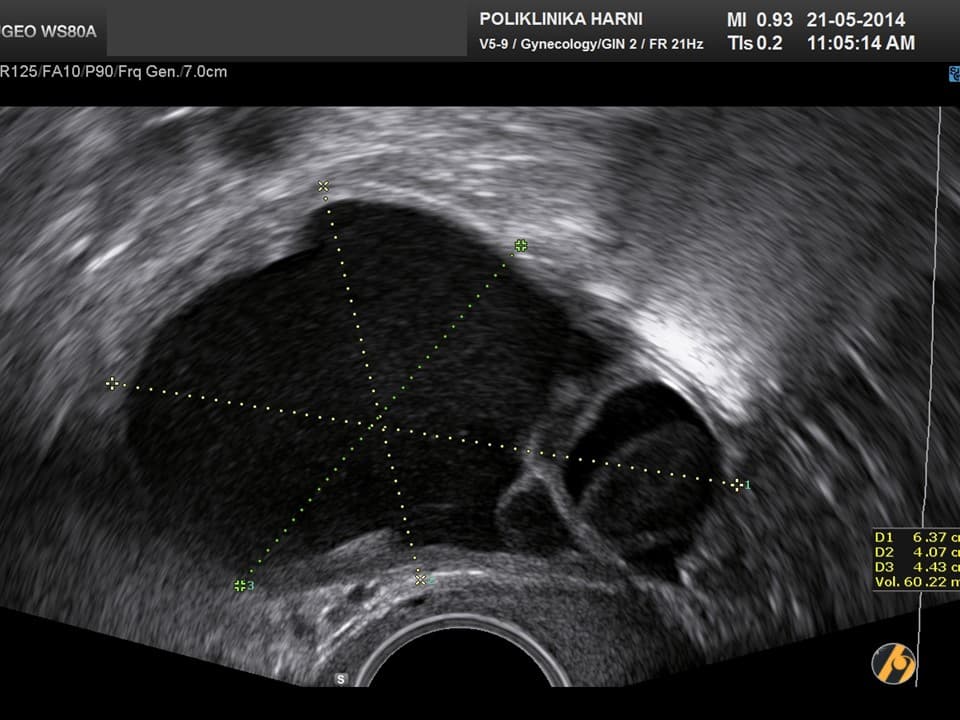

Nažalost, još uvijek ne postoji znanstveno potvrđena dijagnostička metoda koja bi se mogla nazvati metodom probira za karcinom jajnika. Za rano otkriće raka jajnika nužne su i veoma važne redovite ginekološke kontrole uz vaginalni ultrazvuk, odnosno pregled vaginalnim color-Doppler ultrazvukom. U slučaju nejasnih nalaza, uz standardnu laboratorijsku obradu određuju se tumorski biljezi. Optimalni tumorski biljeg za serozne karcinome koji se najčešće javljaju je CA 125, kod rjeđih mucinozni varijanti su to CEA i CA 19-9, a kod endometrioidnih i mucinoznih karcinoma AFP, te ß-hCG kod embrionalnih i koriokarcinoma. U novije vrijeme tumorskim biljezima za rak jajnika su pridodani HE-4 i ROMA indeks.